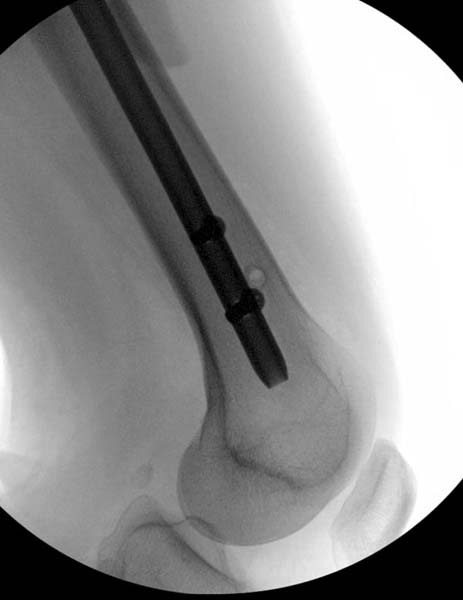

Закрытый БИОС решает множественные проблемы связанные с лечением переломов, но проблема дистальной блокировки без рентгена до сих пор остается нерешенной. Рекламированные производителями приспособления для дистальной блокировки из-за различной кривизны кости не эффективны или стоит очень дорого (Smith&Nephew SureLock). Задержка операции из-за блокировки не всегда удовлетворяет, и многих вынуждает искать альтернативные методы фиксации. С результатами таких действий, остеомиелитом и несращениями, встречаемся в ежедневной жизни..

Для решения проблемы дистальной блокировки компания DigiMed недавно предложила систему блокировки без рентгена. Пока в стране только два набора и только для антеградных гвоздей, но компания работает над созданием устроиства для других гвоздей тоже..

Результат первых случаев показала отсутствие разницы между занятиями на муляжах, а также Workshop и с удивительной точностью вывел латерально над кожей специальное сверло. Дальше по сверлу тонкий направитель и проводится сверление каннюлированным сверлом....